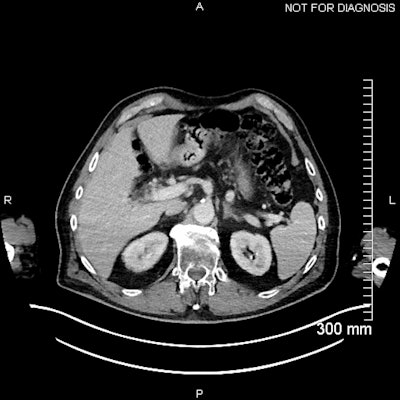

(Above) Fused axial image demonstrates uptake in the celiac ganglia. (Below) Corresponding CT scan. The celiac ganglia are visible. All figures courtesy of Dr. Jonathan Hunter, Dr. Jane Burns, and Prof. Martin O’Connell and presented at ECR 2025.

To accurately interpret nuclear medicine studies, a knowledge of the normal physiological distribution of the radiotracer is required. PSMA expression is present in normal prostatic tissue, though at a low level, and can also be found in the salivary and lacrimal glands, nasal cavity, larynx, liver, spleen, intestines, kidneys, and sympathetic ganglia, the authors pointed out.

The physiological uptake of PSMA ligands in various normal tissues is an important pitfall in PSMA-targeted imaging, they continued. In particular, uptake in sympathetic trunk ganglia can pose challenges to nuclear medicine readers and may mimic lymph nodes. Also, cervical chain and coeliac ganglia may demonstrate higher uptake with F-18 PSMA.